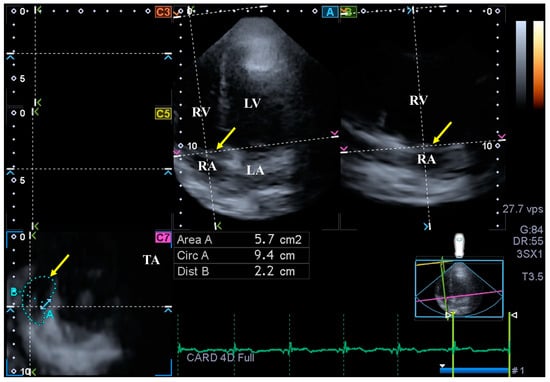

- TA diameter (TAD) was defined as the perpendicular line drawn from the peak of TA curvature to the opposite side of the TA border;

- TA area (TAA) was assessed by planimetry;

- TA perimeter (TAP) was evaluated by planimetry;

- TA fractional shortening (TAFS) = [end-diastolic TAD − end-systolic TAD]/end-diastolic TAD × 100;

- TA fractional area change (TAFAC) = [end-diastolic TAA − end-systolic TAA]/end-diastolic TAA × 100.